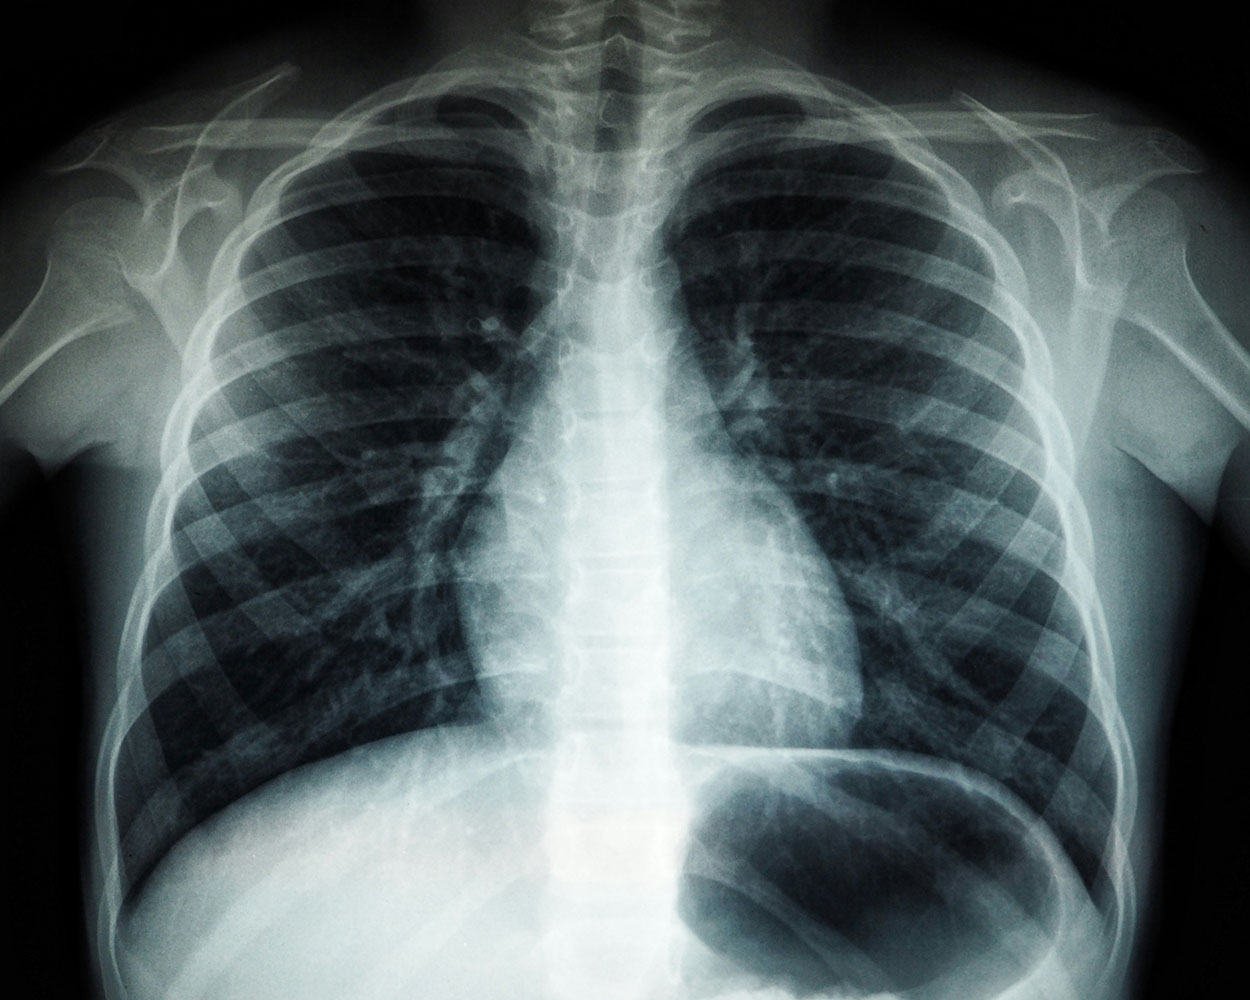

Medical use of radiation centres on a classic trade-off. For example, a chest X-ray exposes patients to ionising radiation, but it can also reveal a life-threatening condition early, allowing for prompt treatment. That’s why radiology follows the rule of justification: only do the scan if its benefit clearly outweighs any small risk. Interestingly, some research even suggests tiny doses might trigger helpful repair processes; the story isn’t black and white.

X-rays are the backbone of medical imaging. From plain radiographs to mammograms and CT scans, they let doctors see bones, lungs, and much more without surgery. Together, X-ray-based tests constitute the bulk of imaging performed in hospitals. Newer CT scanners deliver faster, sharper results, helping clinicians diagnose injuries, cancers, and organ problems more accurately.